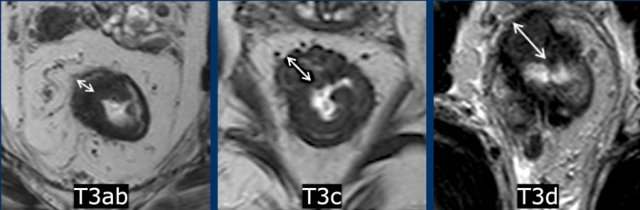

Subclassification

of T3 stage according to invasion depth:

Low-risk T3-tumors:

- T3a: tumor extends <1 mm beyond muscularis propria

- T3b: tumor extends 1-5 mm beyond muscularis propria

High-risk T3-tumors:

- T3c: tumor extends 5-15 mm beyond muscularis propria

- T3d: tumor extends > 15 mm beyond muscularis propria

- T3 MRF+ tumor ≤ 1mm of the MRF